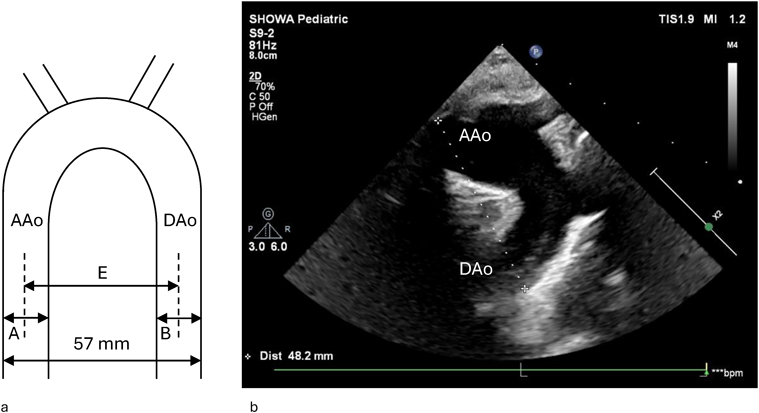

Impella®循環補助用心内留置型ポンプカテーテル(Impella® CP)と静動脈型体外式膜型人工肺により劇症型心筋炎の左室unloadingが著効した12歳男子例—体格の小さい患者における管理上の注意点A 12-year-old male case of successful left ventricular unloading utilizing Impella CP® and veno-arterial extracorporeal membrane oxygenation due to fulminant myocarditis—Precautions for management in patients with small stature